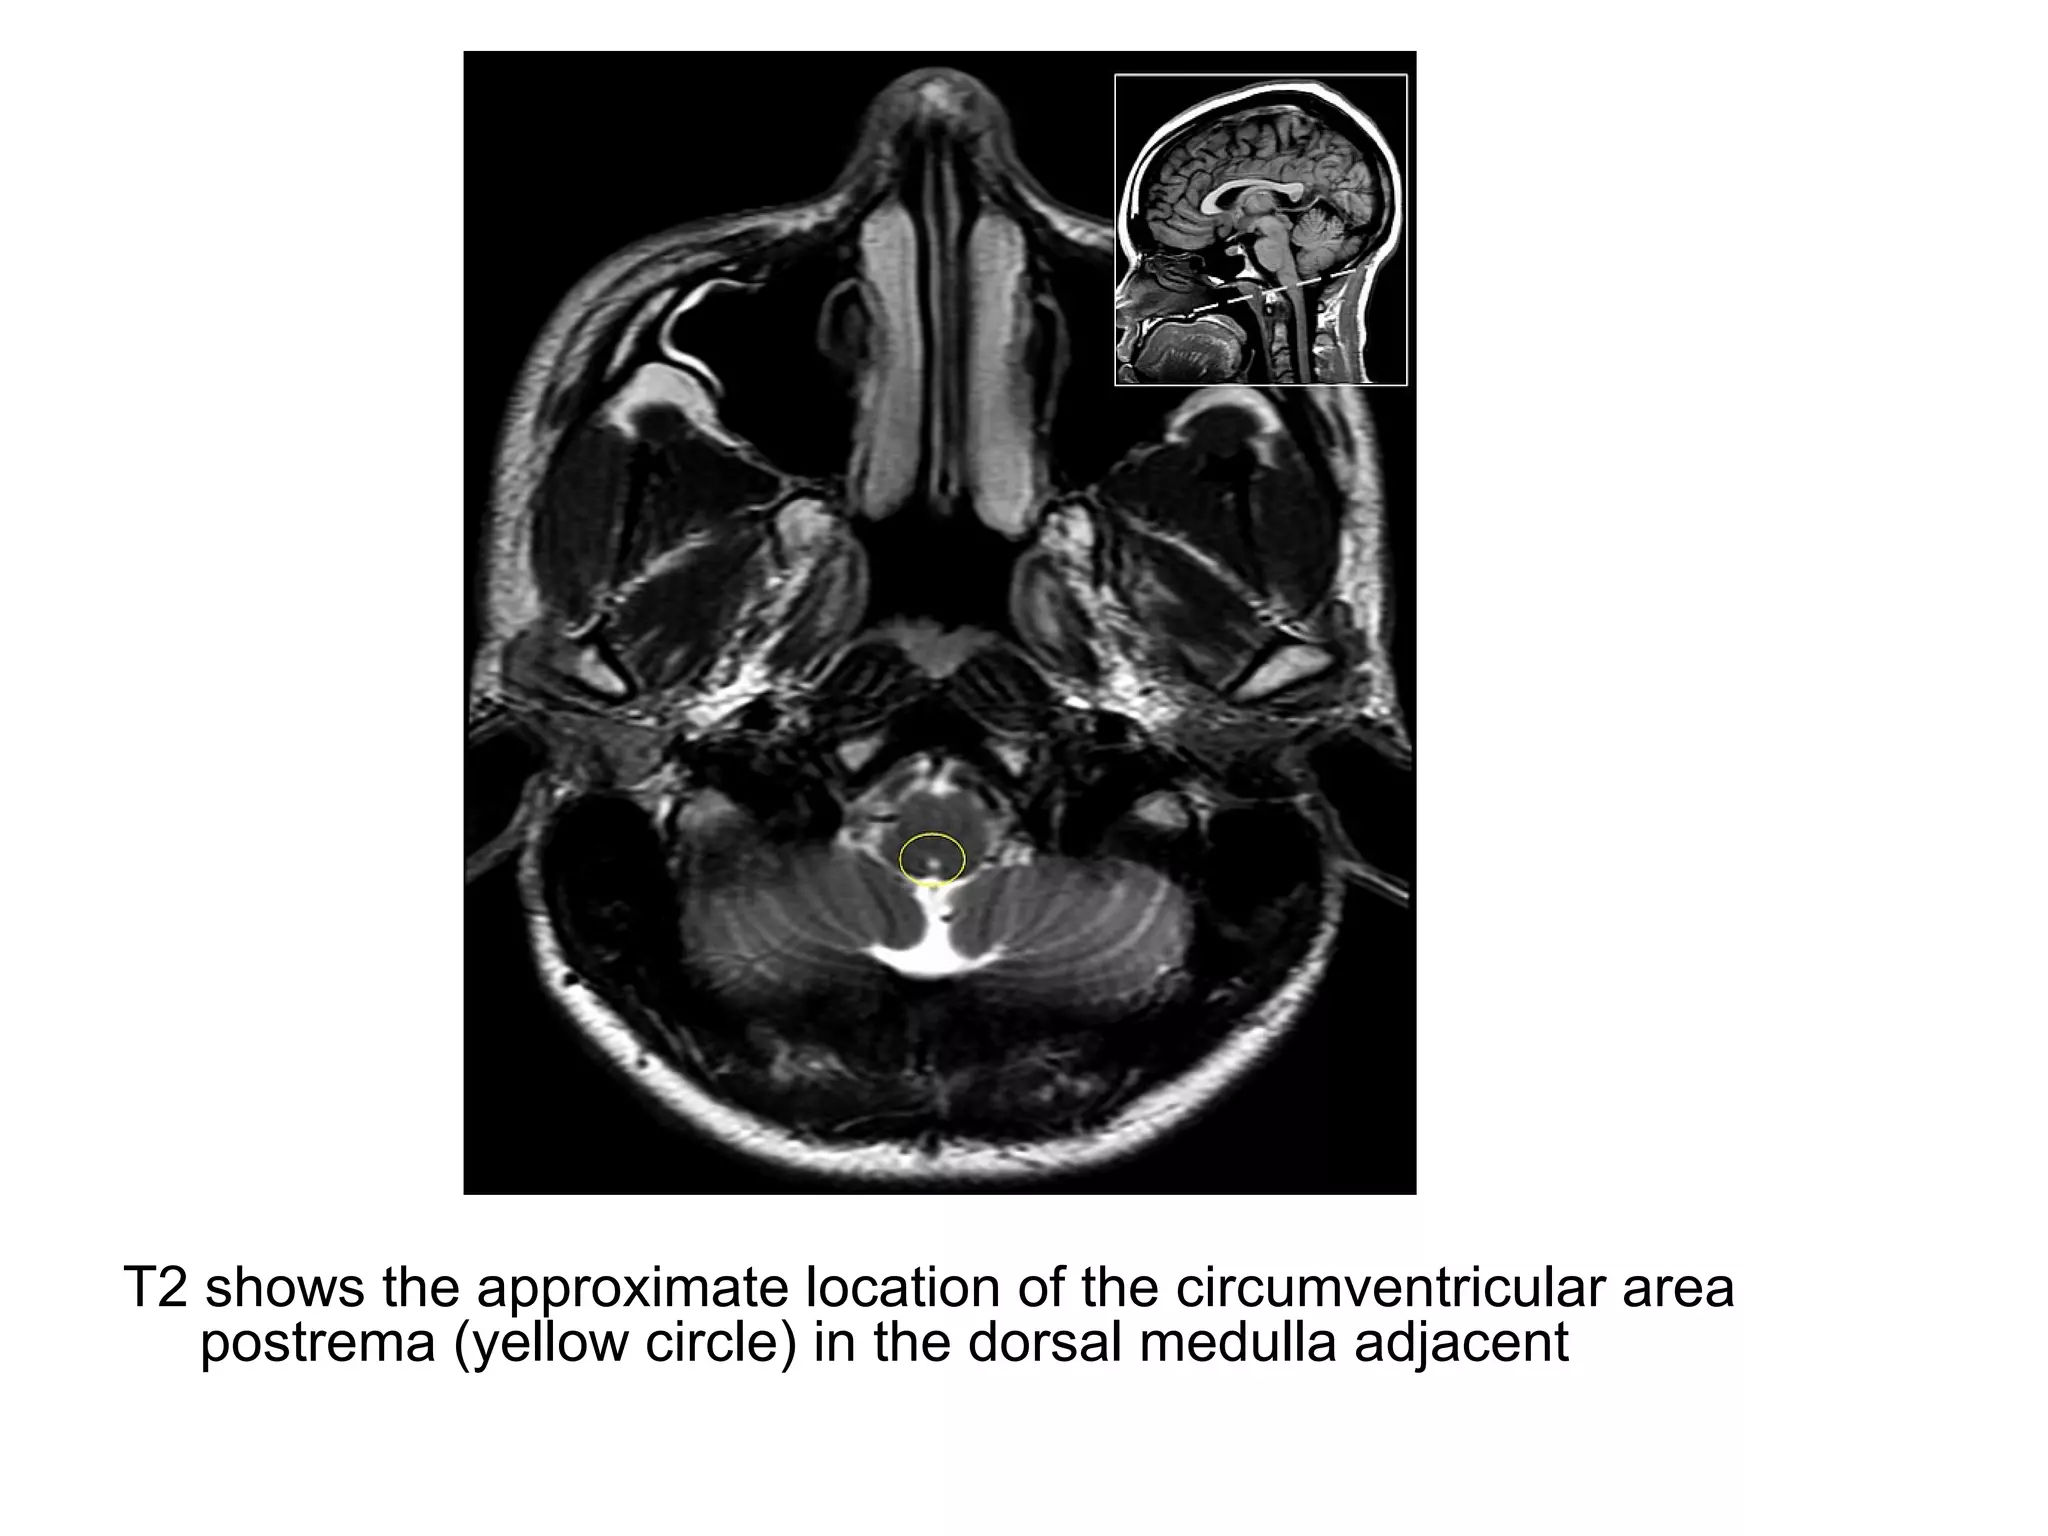

-Several CNS regions don’t have a BBB and therefore

d) Area postrema (controls vomiting, located at inferior

aspect of the 4th

ventricle)

T2 shows the approximate location of the circumventricular area

postrema (yellow circle) in the dorsal medulla adjacent

T2 shows theapproximate location of the circumventricular area postrema (yellow circle) in the dorsal medulla adjacent